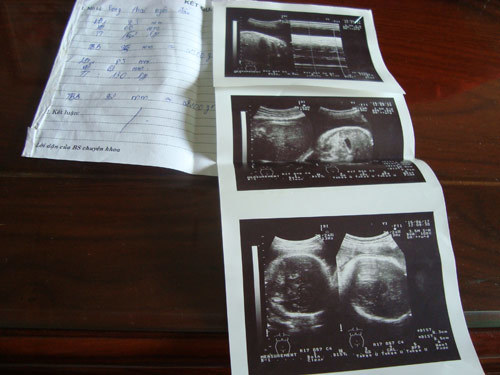

5 năm sau ngày cưới, bước chân của anh Dũng và chị Thắm đã đi đến bao nhiêu nẻo đường, bệnh viện để chữa trị với mong muốn có được mụn con. ![]() Tờ phiếu khám bệnh và kết quả siêu âm anh chị vẫn giữ lại để sau này làm kỉ niệm. ![]() Hai cô công chúa đáng yêu của anh chị mới được hơn một tháng tuổi. ![]() Sau hơn một tháng, hai bé đã mập mạp lên khá nhiều so với khi chào đời. ![]() Anh Dũng cẩn thận chăm con hỗ trợ vợ hàng ngày. ![]() Bé Yến Nhi cất tiếng khóc chào đời sau nhưng lại nặng hơn chị 1 kg. ![]() Bé Hà Nhi chào đời với cân nặng 2,1 kg và sức khỏe hoàn toàn bình thường. ![]() Anh Dũng nâng niu con từng li từng tí. Sau một tháng được lên chức bố, anh đã quen với công việc sữa, bỉm hàng ngày. ![]() Thỉnh thoảng, anh chị vẫn lấy giấy tờ, kết quả khám thai trong suốt thời gian thai kì để ngắm nghía và kể lại hành trình gian nan với mọi người. ![]() May mắn gia đình anh chị ở cạnh nhà bố mẹ và người thân nên luôn có mọi người hỗ trợ chăm các bé. |